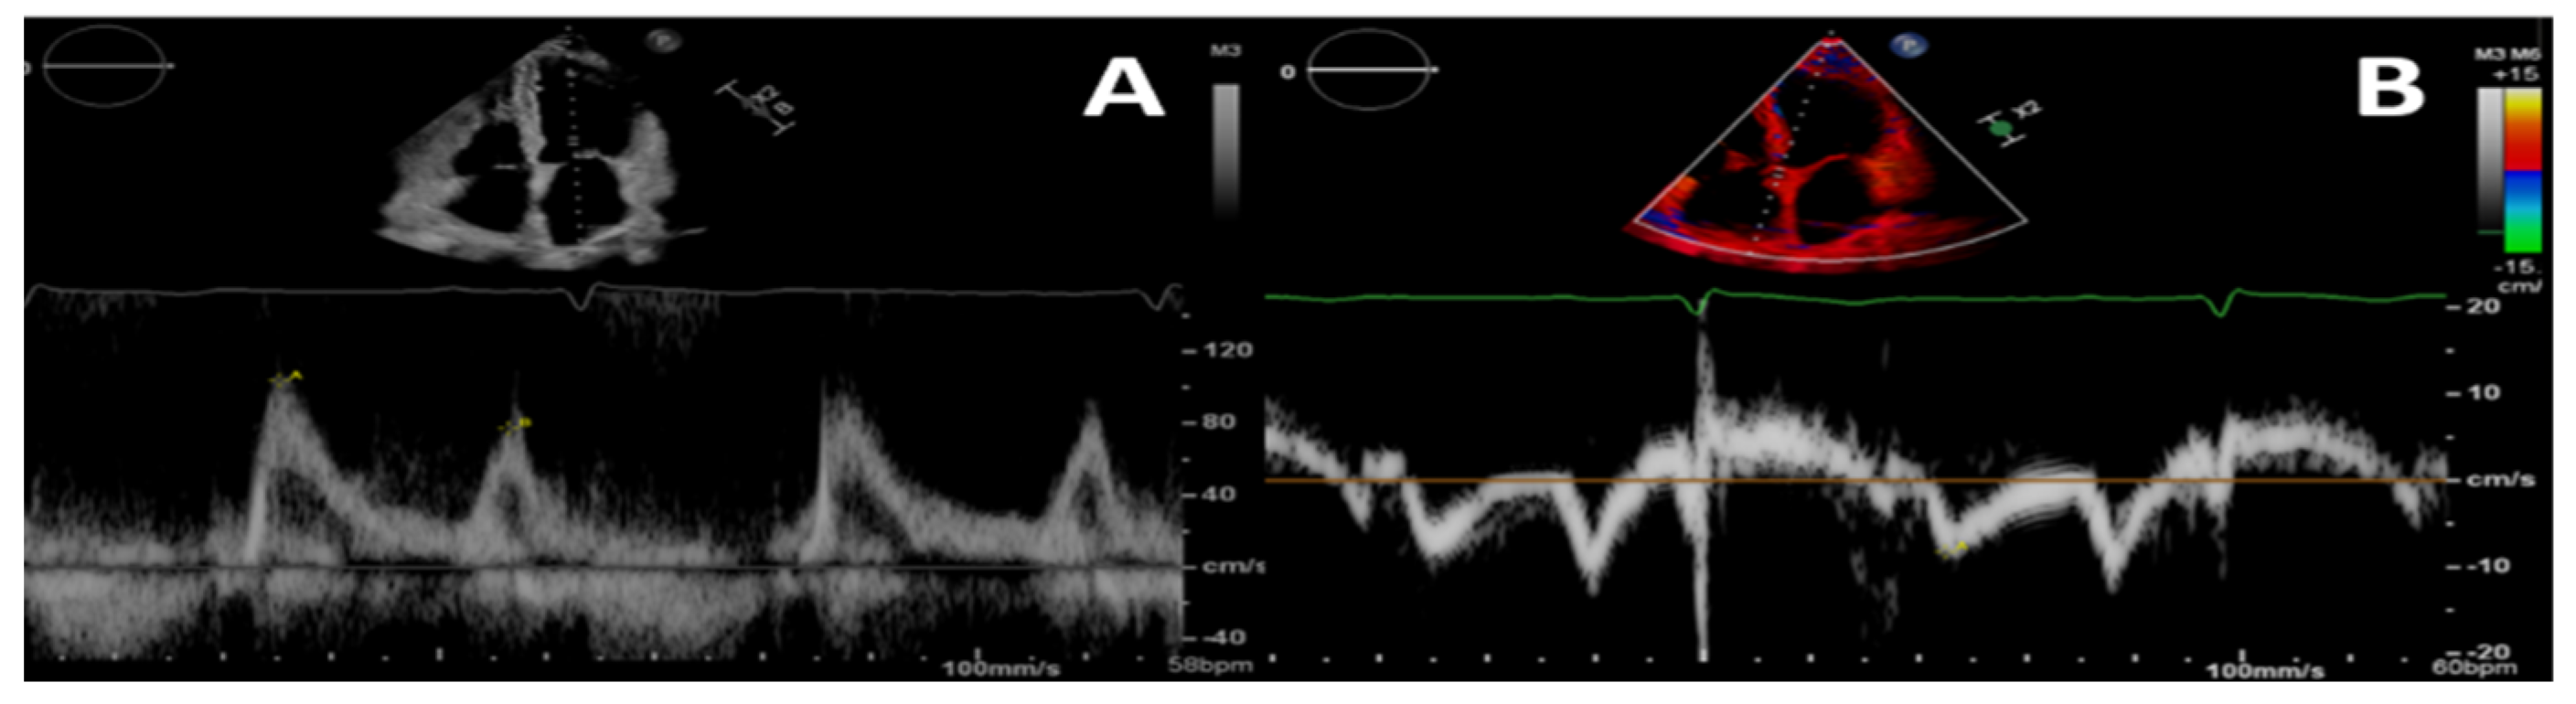

2.2. Diastolic Function

2.3. Systolic Function

- Nagueh, S.F.; Smiseth, O.A.; Appleton, C.P.; Byrd, B.F., 3rd; Dokainish, H.; Edvardsen, T.; Flachskampf, F.A.; Gillebert, T.C.; Klein, A.L.; Lancellotti, P.; et al. Recommendations for the Evaluation of Left Ventricular Diastolic Function by Echocardiography: An Update from the American Society of Echocardiography and the European Association of Cardiovascular Imaging. J. Am. Soc. Echocardiogr. 2016, 29, 277–314. [Google Scholar] [CrossRef]

- Suh, S.Y.; Kim, E.J.; Choi, C.U.; Na, J.O.; Kim, S.H.; Kim, H.J.; Han, S.W.; Chung, S.M.; Ryu, K.H.; Park, C.G.; et al. Aortic Upper Wall Tissue Doppler Image Velocity: Relation to Aortic Elasticity and Left Ventricular Diastolic Function. Echocardiography 2009, 26, 1069–1074. [Google Scholar] [CrossRef]